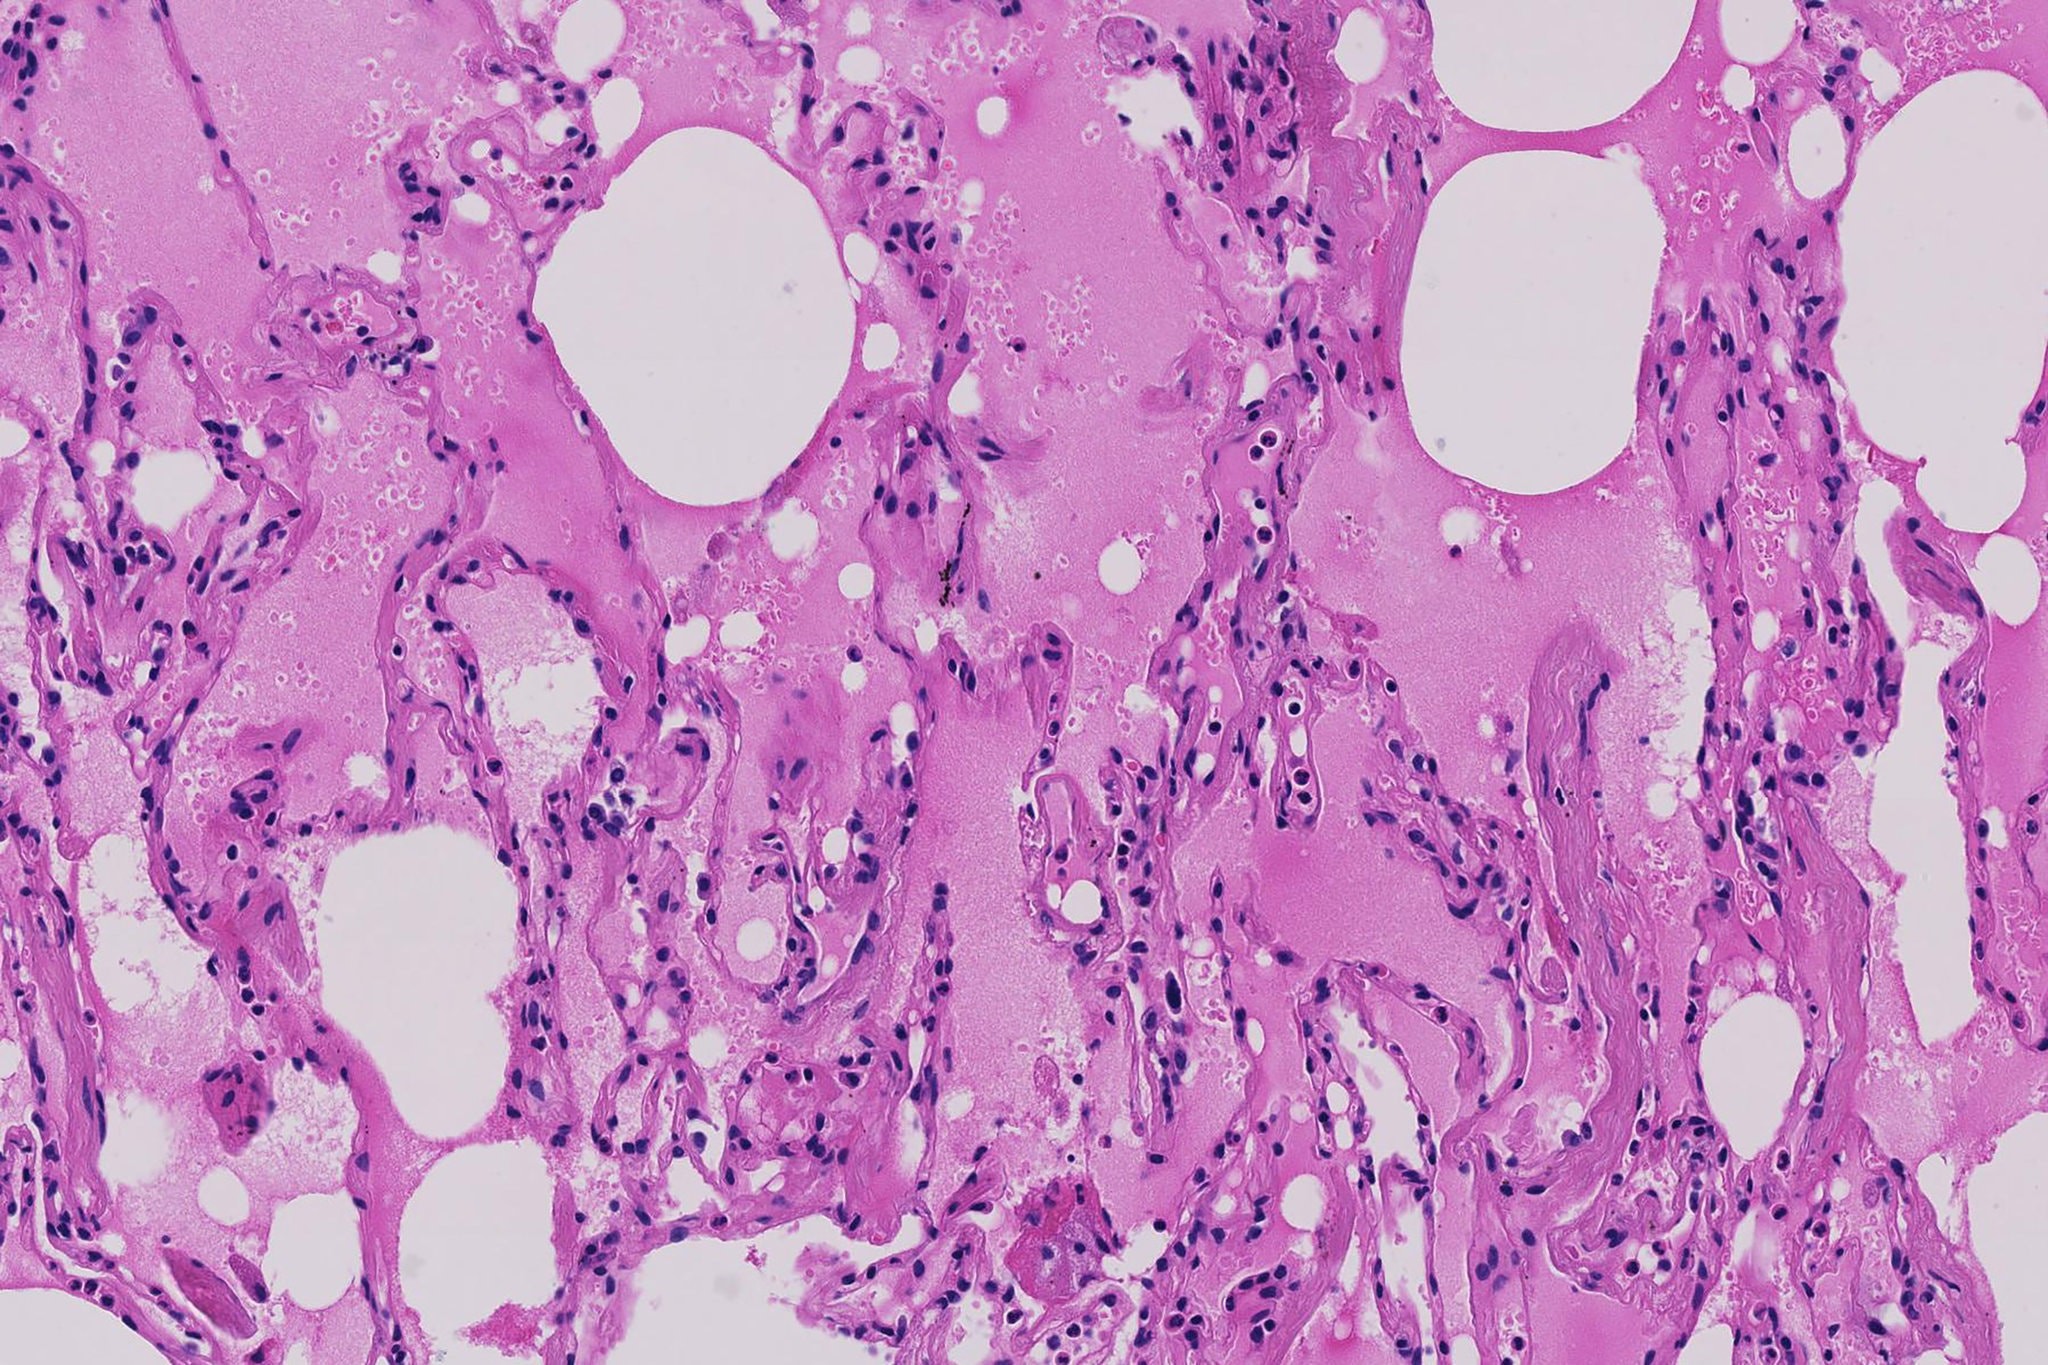

Ποια «τροχιά» έχει ο ιός στους πνεύμονες;

Ο Δρ Ο Shu-Yuan Xiao, καθηγητής παθολογίας στο Τμήμα Ιατρικής του Πανεπιστημίου του Σικάγο, εξέτασε τις αναφορές παθολογίας για τους ασθενείς με κορωνοϊό στην Κίνα. Είπε ότι ο ιός φαίνεται να ξεκινά σε περιφερικές περιοχές και στις δύο πλευρές του πνεύμονα και μπορεί να πάρει λίγο χρόνο για να φτάσει στην άνω αναπνευστική οδό, την τραχεία και άλλους κεντρικούς αεραγωγούς.

Ο Δρ Xiao, ο οποίος επίσης διατελεί διευθυντής του Κέντρου Παθολογίας και Μοριακής Διαγνωστικής στο Πανεπιστήμιο Wuhan, δήλωσε ότι το πρότυπο βοηθάει να εξηγηθεί γιατί στο Wuhan, όπου ξεκίνησε η εκδήλωση, πολλές από τις πρώτες περιπτώσεις δεν εντοπίστηκαν αμέσως.

Το αρχικό θεραπευτικό σχήμα σε πολλά Κινέζικα νοσοκομεία δεν ανίχνευε πάντα λοίμωξη στους περιφερικούς πνεύμονες, έτσι μερικοί άνθρωποι με συμπτώματα στέλνονταν στο σπίτι χωρίς θεραπεία. «Είχαν πάει είτε σε άλλα νοσοκομεία για να αναζητήσουν θεραπεία είτε έμειναν σπίτι μολύνοντας την οικογένειά τους», είπε. «Αυτός είναι ένας από τους λόγους για τους οποίους υπήρξε τόσο μεγάλη εξάπλωση».

Μια πρόσφατη μελέτη από μια ομάδα ερευνητών της Ιατρικής Σχολής του Icahn στο Mount Sina διαπίστωσε ότι περισσότεροι από τους μισούς από τους 121 ασθενείς στην Κίνα είχαν κανονικές αξονικές τομογραφίες νωρίς στην ασθένειά τους.

Η μελέτη και η εργασία του Δρ. Xiao δείχνει ότι καθώς η ασθένεια εξελίσσεται, οι αξονικές τομογραφίες δείχνουν «αχνά αχνά πράγματα», ένα είδος θολού ματιού σε μέρη του πνεύμονα που είναι εμφανή σε πολλούς τύπους ιογενών αναπνευστικών λοιμώξεων. Αυτές οι αδιαφανείς περιοχές μπορούν να διασκορπιστούν και να διογκωθούν σε μέρη καθώς η ασθένεια επιδεινώνεται, δημιουργώντας κάτι που οι ακτινολόγοι αποκαλούν ένα μοτίβο “crazy paving” στη σάρωση.

Ο Δρ Xiao διεξήγαγε παθολογικές εξετάσεις δύο ατόμων στην Κίνα που πήγαν σε νοσοκομείο στο Wuhan τον Ιανουάριο για διαφορετικό λόγο – χρειάζονταν χειρουργική επέμβαση για καρκίνο του πνεύμονα πρώιμου σταδίου – αλλά τα αρχεία αργότερα έδειξαν ότι είχαν επίσης λοίμωξη από κορονοϊό, το οποίο το νοσοκομείο δεν αναγνώριζε εκείνη την εποχή.

Ούτε ο καρκίνος του πνεύμονα του ασθενούς προχώρησε αρκετά ώστε να τα σκοτώσει, είπε.

Ένας από αυτούς τους ασθενείς, μια 84χρονη γυναίκα με διαβήτη, πέθανε από πνευμονία που προκλήθηκε από κορωνόϊό, εξήγησε ο Δρ Xiao. άλλος ασθενής, ένας 73χρονος άνδρας, ήταν κάπως υγιέστερος, με ιστορικό υπέρτασης που είχε καταφέρει να ελέγξει καλά για 20 χρόνια. Ο Δρ Xiao είπε ότι ο άντρας είχε επιτυχημένη χειρουργική επέμβαση για να αφαιρέσει έναν όγκο του πνεύμονα, απολύθηκε και εννέα ημέρες αργότερα επέστρεψε στο νοσοκομείο.